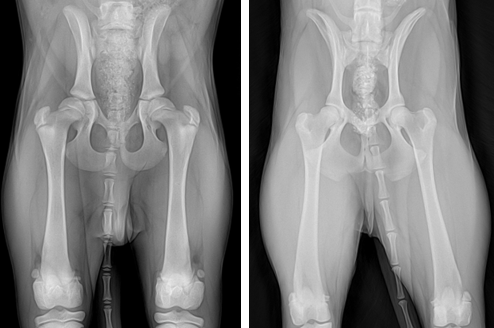

일반적인 Hip extension 촬영법 펜힙(Penn HIP) 촬영법

위 사진은 4개월령 루키의 같은날 촬영한 방사선 영상입니다.

골두가 들어가는 골반의 관골구에 빨간색의 가상의 원을 그리고 허벅지뼈의 골두에 가상의 원을 그린 후 노란색원이 빨간색원에서얼마나 빠져있는지 평가를 합니다. 같은 아이의 방사선 영상인데도 두 영상의 차이가 극명하게 드러납니다.

펜힙(Penn HIP)검사를 진행하지 않았다면 루키는 고관절 고위험군인지 인지하지 못하고 치료시기를 놓쳐 성견이 된 후 양측 고관절의 퇴행성 관절염이 발생했을 가능성이 매우 높습니다.